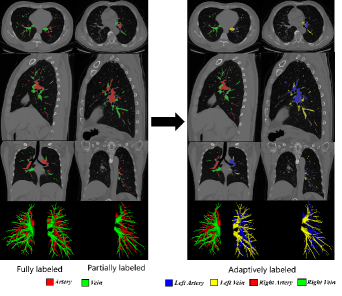

Refer to caption

Figure 2: This pic shows the adaptation of our data. We only change the label of the artery/vein without making any other adjustments.

We present a large-scale pulmonary vessel segmentation dataset collected from a real-world local hospital, comprising a total of 718 3D CT volumes provided in compressed NIFTI (.nii.gz) format. Among these, the pulmonary arteries and veins are manually annotated, where 79 CT scans are fully labeled and 639 CT scans are half-labeled, indicating the involvement of either the left lung or the right lung, as depicted in Fig. 2. In clinical practice, most patients typically exhibit disease in only one lung, with only a small proportion affected in both lungs. Therefore, it is reasonable to compile a dataset that combines fully labeled and half-labeled CT scans. The sizes of these CT volumes range from 512×512×169 to 512×512×985, with varying slice thicknesses from 0.62 to 1.25 mm. Annotations are obtained from five junior clinicians (with one to five years of experience) who used MIMICS to manually refine the segmentation results under the supervision of two board-certified radiologists. Finally, a senior radiologist with over ten years of experience verified and refined the annotations. We will make the dataset and annotations publicly available upon the acceptance of this work. We divide the labeled data into training, validation, and test sets at a ratio of 7:1:2, where 502 volumes are designated as the Training Dataset; 72 volumes are allocated for validation and 143 volumes for testing. Results are shown on Tabel IV. All experiments are reported as meanstdmean_{std} with three repeated trials in this work.

Label augmentation: We convert the three-class segmentation task (i.e. background, artery, vein) into a five-class segmentation task. For example, we represent 1 for the left pulmonary artery, 2 for the left pulmonary vein, 3 for the right pulmonary artery, 4 for the right pulmonary vein and 0 for the background. This method can improve the model’s performance significantly, not only for us but other state-of-the-art methods as well. It can be seen from Table II that when adding the half-labeled data into training without adaptive augmentation, the DSC slightly increased from 66.14% to 67.19%. This means that the incomplete label is not exploited in this setting. Instead, our method utilizes these settings and gets the full potential of the half-labeled data. Therefore, we choose a simple but efficient augmentation for our incomplete label.